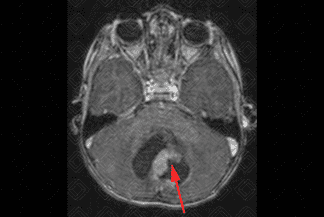

Texto alternativo para a imagem Créditos : Dra. Elazir Mota - Rio de Janeiro

Descrição da imagem: Ressonância magnética do crânio. Sequência T2: lesão com sinal muito elevado na sua porção líquida (lembrar que água/líquido “brilham” em T2) e, além disso, observa-se que a porção sólida do tumor apresenta tênue hipersinal em relação ao parênquima adjacente (setas vermelhas).